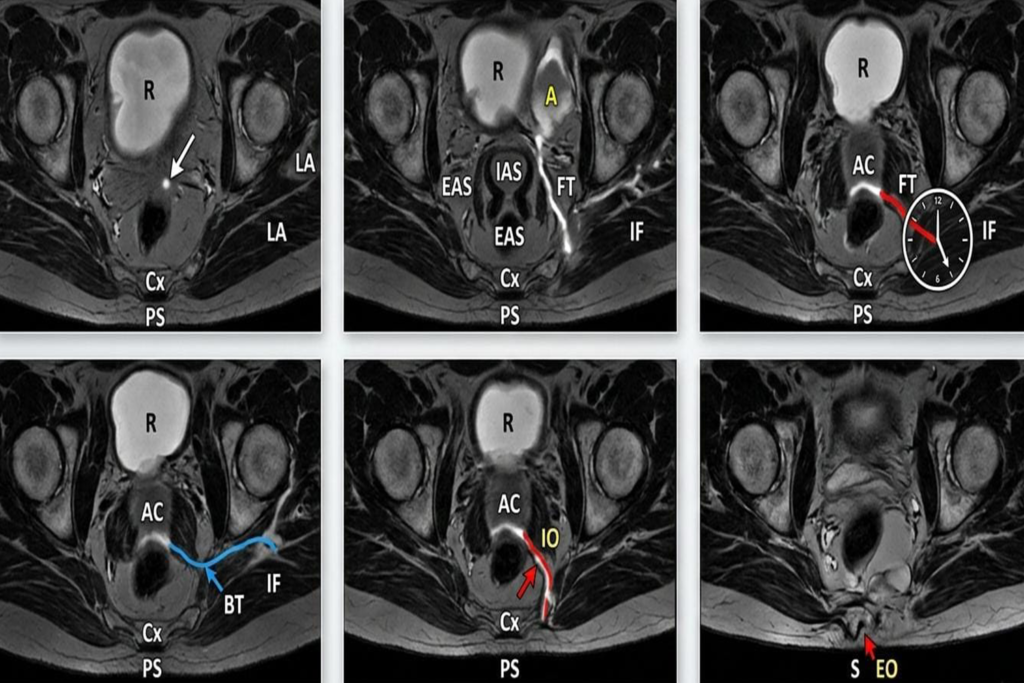

Diagnosis: Mapping the Tract

A physical examination by a specialist is the first step. To ensure no “hidden branches” are missed, we utilize advanced imaging:

- Digital Rectal Examination (DRE): To feel the internal opening.

- MRI Fistulogram: The “gold standard” for 2026, providing a high-definition map of the entire tract and its secondary branches.

- Endoanal Ultrasound: To see the relationship between the fistula and the sphincter muscles.